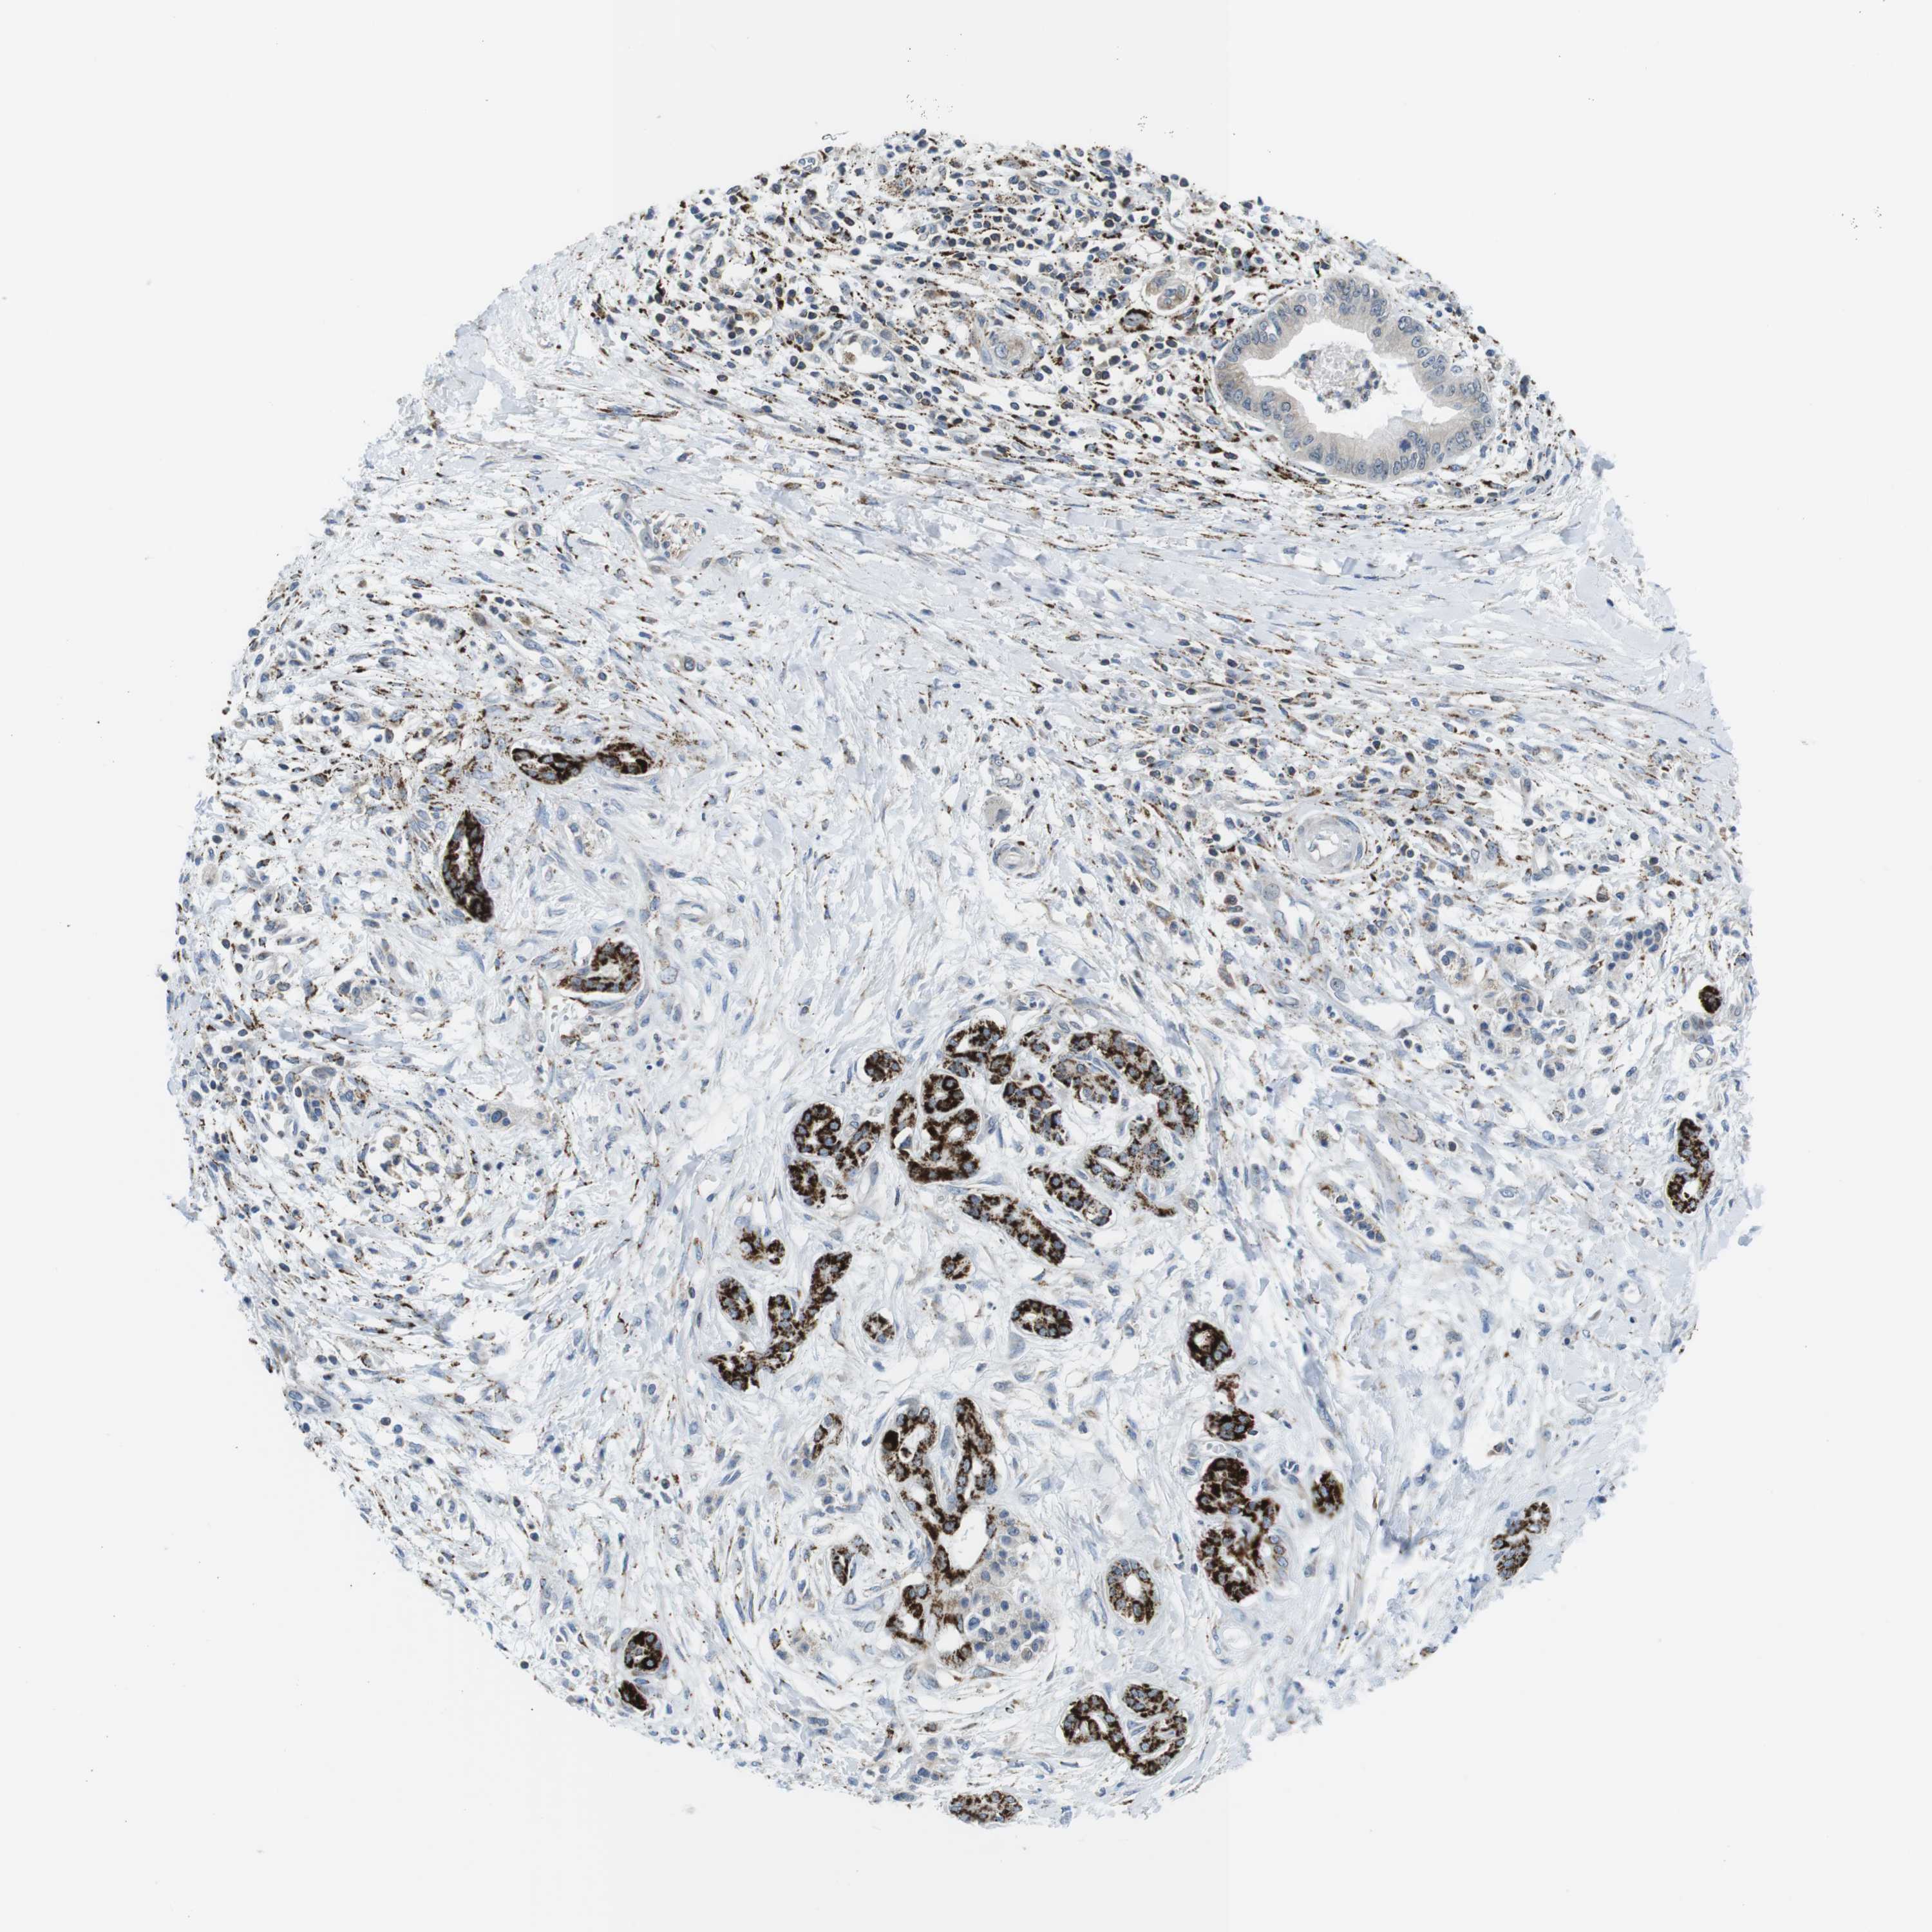

PANCREATIC CANCER - Protein expressioni

A mouse-over function shows sample information and annotation data. Click on an image to view it in a full screen mode. Samples can be filtered based on level of antibody staining by selecting one or several of the following categories: high, medium, low and not detected. The assay and annotation is described here.

Note that samples used for immunohistochemistry by the Human Protein Atlas do not correspond to samples in the TCGA dataset.

Antibody stainingi

Antibody staining in the annotated cell types in the current human tissue is reported as not detected, low, medium, or high, based on conventional immunohistochemistry profiling in selected tissues. This score is based on the combination of the staining intensity and fraction of stained cells.

Each image is clickable and will lead to virtual microscopy that enables deeper exploration of all samples and also displays staining intensity scores, fraction scores and subcellular localization as well as patient and tissue information for each sample.

Antibody HPA014849

Staining

High

Medium

Low

Not detected

Intensity

Strong

Moderate

Weak

Negative

Quantity

>75%

75%-25%

<25%

None

Location

Nuclear

Cytoplasmic/membranous

Cytoplasmic/membranous,nuclear

Adenocarcinoma, NOS